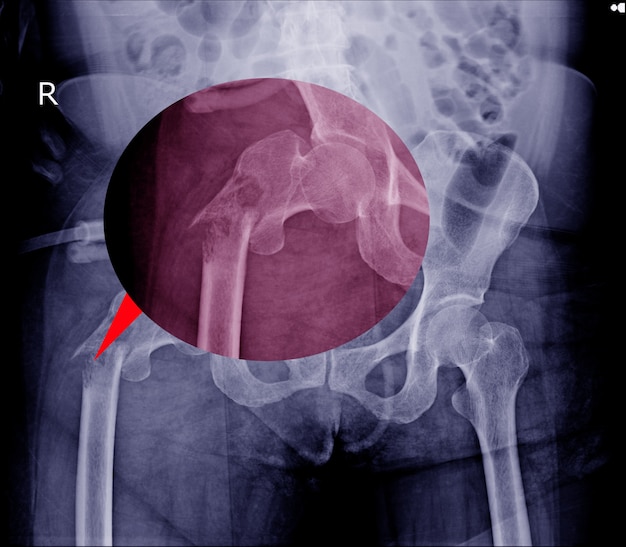

Aby postawić diagnozę, konieczne są zaawansowane badania, takie jak zdjęcia rentgenowskie oraz biopsje.

- złamania szyjki udowej,

- które mogą prowadzić do wielu poważnych problemów zdrowotnych,

- niestety, takie urazy zwiększają również ryzyko śmierci,

- zwłaszcza wśród seniorów.